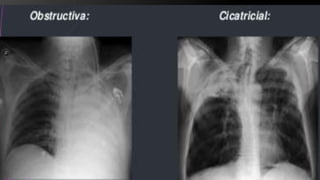

Atelectasias La palabra atelectasia se utiliza de manera

especifica para denotar disminución de gas en el pulmón

asociada con disminución del volumen pulmonar

que no implica por necesidad un incremento en la radioopacidad.

•Ocurren cuando la comunicación entre el alveolo y la tráquea esta obstruida.Atelectasias por

reabsorción

•Es la pérdida de volumen que acompaña a grandes procesos que ocupan espacio en el

tórax

Atelectasias por

relajación

•Es una atelectasia con vías aéreas permeables, que probablemente está relacionada con

problemas del surfactanteAtelectasias adhesivas

•Es una pérdida de volumen que acompaña a la fibrosis pulmonar y que es generalmente

secundaria a lesiones inflamatorias crónicas

cicatrización

Atelectasias La palabraatelectasia se utiliza de manera especifica para denotar disminución de gas en el pulmón asociada con disminución del volumen pulmonar que no implica por necesidad un incremento en la radioopacidad. •Ocurren cuando la comunicación entre el alveolo y la tráquea esta obstruida.Atelectasias por reabsorción •Es la pérdida de volumen que acompaña a grandes procesos que ocupan espacio en el tórax Atelectasias por relajación •Es una atelectasia con vías aéreas permeables, que probablemente está relacionada con problemas del surfactanteAtelectasias adhesivas •Es una pérdida de volumen que acompaña a la fibrosis pulmonar y que es generalmente secundaria a lesiones inflamatorias crónicas Atelectasias por cicatrización